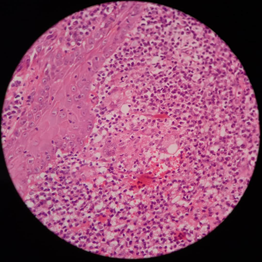

We suspected that the site of the fishing net and fish-carrying bag on the back of the patient's shoulder was similar to Mycobacterium marinum inoculation. Skin biopsies were taken for histopathological examination, and it showed the epidermis with acanthosis and parakeratosis. The dermis showed severe infiltration of neutrophils and lymphoplasma cells with the presence of few giant cells and poorly defined granulomas indicating an acute or chronic necrotizing granulomatous inflammatory process due to an atypical mycobacterial infection, so M. marinum diagnosis was confirmed via histological examination. (Ziehl–Neelsen and Periodic acid–Schiff (PAS) staining were negative).

The patient managed well with appropriate treatment. Within three weeks of starting treatment, signs of improvement began, prescribed with oral clarithromycin 500 mg orally, b.i.d, rifampin at a dose of 600 mg daily in combination, and co-trimoxazole 960 mg b.i.d., to be continued for at least three months (Figure 2).

Figure 2 Severe infiltration of neutrophils and lymphoplasma cells with the presence of some giant cells and poorly defined granulomas (Hematoxylin and eosin; original magnification 400x).

M. marinum typically develops after minor injury or contact with fish.14 In our case, also, M. marinum infection inoculates c by minor damage, which Carrying fishing nets and fish carrying bags on his shoulder caused it. Histopathologic findings from biopsied sites demonstrate non-specific infiltrates and granulomas. Tuberculoid, sarcoid, and nodule-like granulomas have been reported. Moreover, Histopathologic findings of M. marinum consist of granulomatous inflammatory processes, acanthosis, and parakeratosis in the dermis. These granulomas may be presented with central necrosis and suppuration.15 In the present case report, a biopsy was performed

Which revealed an epidermis with acanthosis and parakeratosis, and the dermis shows severe infiltration of neutrophils and lymph plasma cells with the presence of some giant cells and poorly defined granulomas (Hematoxylin and eosin staining) and Ziehl–Neelsen staining and Periodic acid–Schiff (PAS) staining were negative.